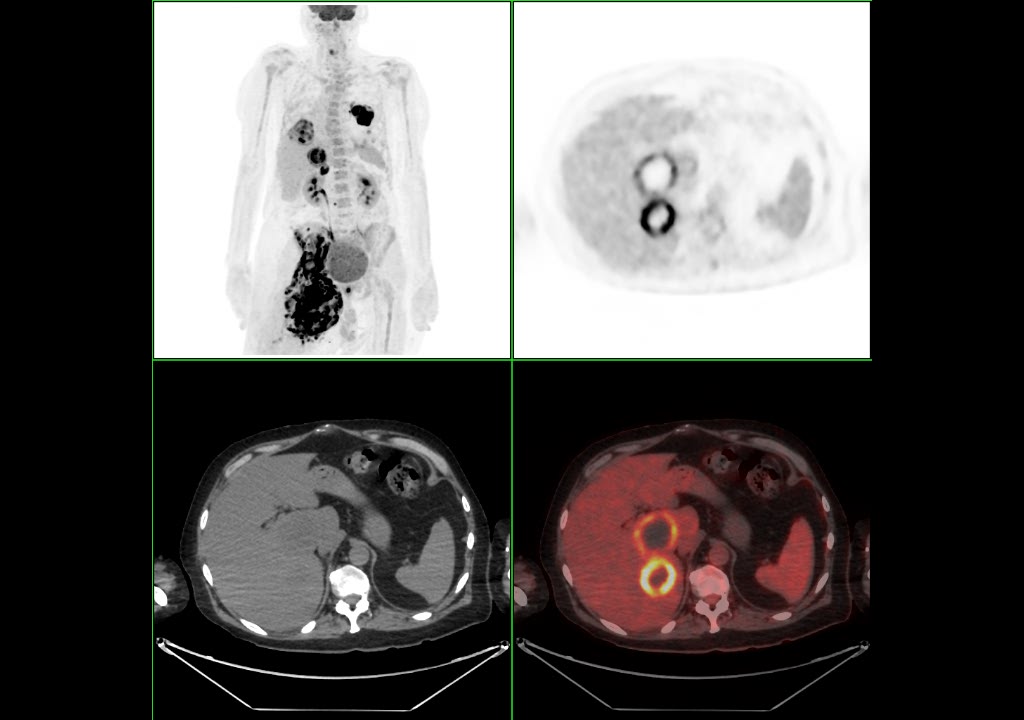

Bilan d’extension d’un adénocarcinome pulmonaire lobaire inférieure gauche:

ADK peu différentié PDL1 en attente, Kras et TP53 muté (cT2aN1M1c).

Suspiscion d’encéphalite paranéoplasique et lésions suspectes hépatiques

Masse pulmonaire du lobe inférieur gauche, en rapport avec la lésion primitive connue, associée à une lymphangite carcinomateuse et un nodule satellite hypermétabolique.

Condensation pulmonaire hypermétabolique abcédée du lobe inférieur droit.

Masse collectée en fosse iliaque droite, développée en regard du muscle iliaque droit, s’étendant à la région des adducteurs et du triangle fémoral homolatéraux, lobulée, de métabolisme hétérogène.

Extension hypermétabolique secondaire hilaire gauche, hépatique, surrénalienne droite et ganglionnaire rétro-cave

Cette présentation était intéressante car l’extension hépatique et ganglionnaire rétro-cave peut également se voir dans les tumeurs desmoplastiques. Il était donc difficile de faire la part des choses entre une extension secondaire d’origine pulmonaire ou tumorale desmoplastique.